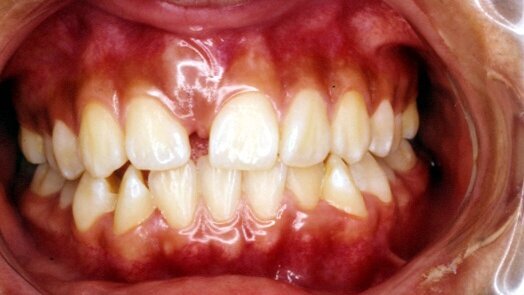

Caso 1 Paciente de sexo femenino de 12 años de edad que presenta diastema antero superior. A la palpación se oberva aumento de volumen en zona vestibular a nivel de línea media. Se toma rx panorámica y periapical, en la que se evidencia diente supernumerario mesiodens a nivel de piezas 11y 21.